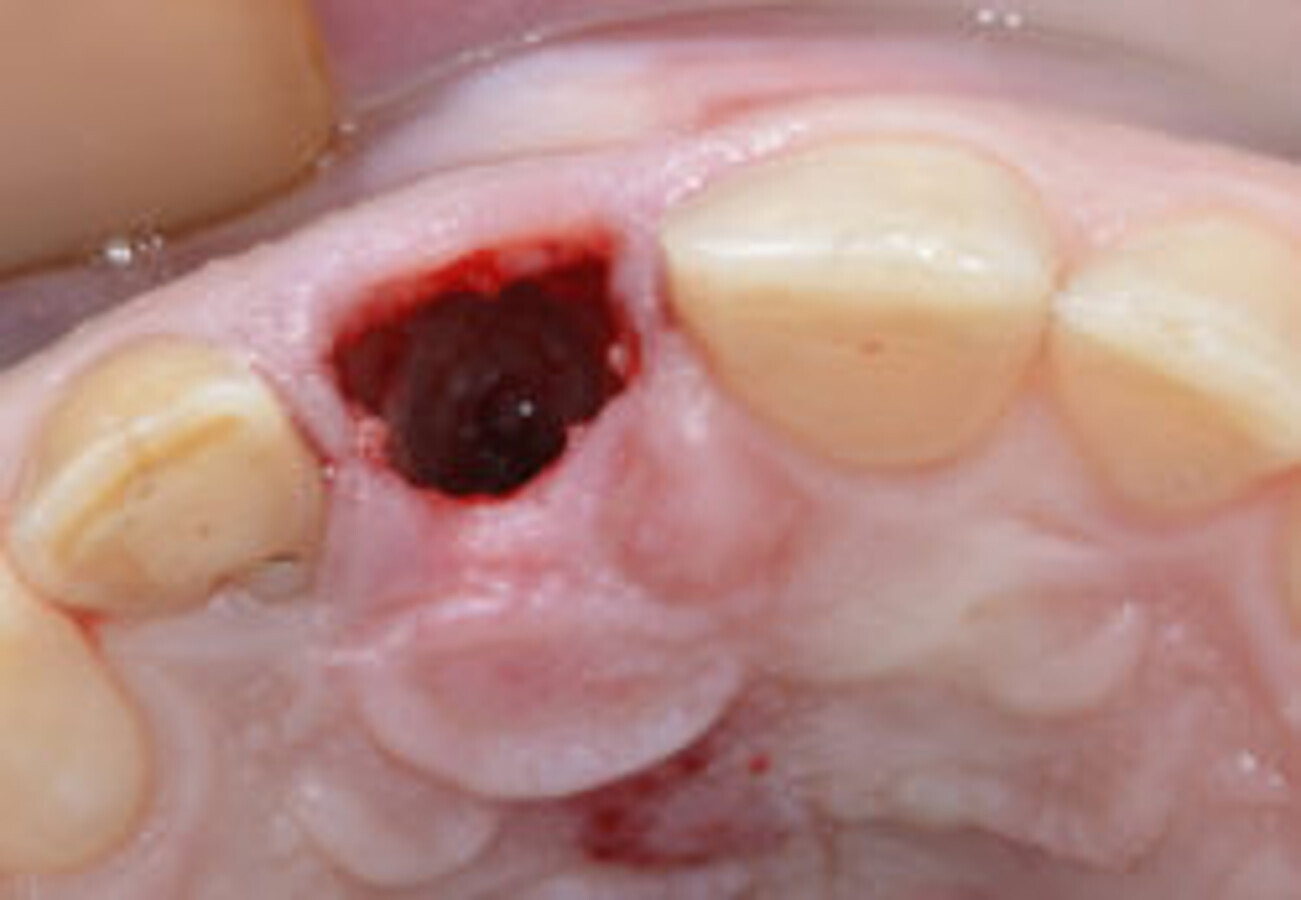

图9. #11骨折吸收处可见肉芽组织。

图11.#11创伤性拔除后的清洁窝洞。

前期准备充分后,拔除患牙。患牙骨折吸收区明显可见肉芽组织(图9),使用Er:YAG激光治疗仪将其移除(H14型手持器械,欧洲之星Fotona;图10)。拔牙过程无创伤,创口干洁,可以行种植术(图11)。